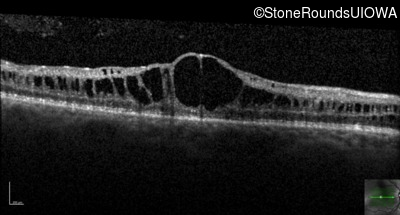

Optical Coherence Tomography - Right - 20/80

Exemplar / OCT Stack

OCT Stack